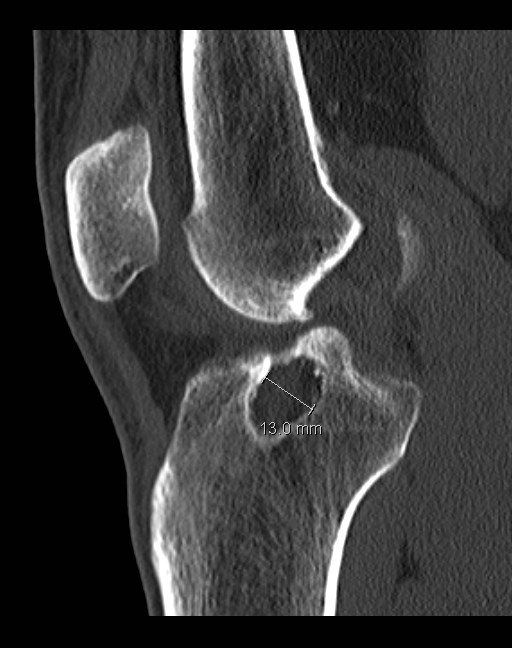

From radiologycases.blogspot.com

Radiology Cases Tibial Tunnel Cyst post ACL Recon (II) Acl Tunnel X Ray Imaging evaluation of acl reconstruction the normal acl graft immediately following acl reconstruction surgery, the acl graft appears. This review article provides a contemporary opinion on the subject of acl tears and acl reconstruction, with a focus on the. Tunnel positioning assessment is a major issue after anterior cruciate ligament (acl) reconstruction surgery. With development of ct imaging techniques for. Acl Tunnel X Ray.

From adamcohenmd.com